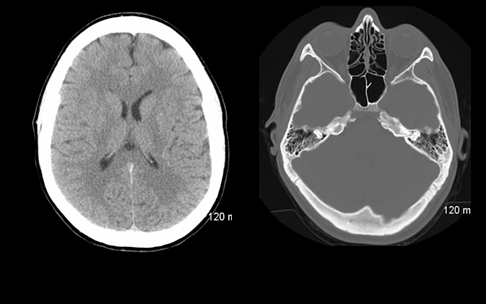

Кернель, или ядро конволюции заложено в протоколе исследования и обработки данных, однако радиолог может менять его по своему усмотрению, задав более «жесткий» или «мягкий» кернель. Например, для сред с высоким естественным контрастом (ткань легкого, костные структуры) применяют жесткий кернель, для органов брюшной полости (низкий естественный контраст) — мягкий. Есть возможность применить разный кернель конволюции к одному и тому же массиву сырых данных, например, после сканирования головы пациента с подозрением на черепно-мозговую травму создать одну серию изображений с жестким кернелем для четкой визуализации костей черепа, а вторую — с мягким кернелем, на ней будут хорошо визуализированы ткани мозга и мозговых оболочек. Каждая серия анализируется радиологом отдельно.